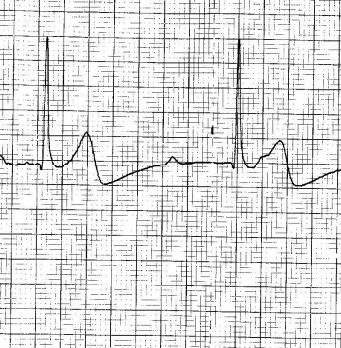

EsAmb : ECG N°2

Publié le 16.02.2016

Les études de cas sur les ECG par les étudiants ambulanciers de Genève avec les commentaires et la correction du Dr Marc Zimmermann (cardiologue à Genève) : ECG N°2 par Emmanuelle BLASER Voir l'étude de cas ECG N°2 Ce…

EsAmb : ECG N°4

Les études de cas sur les ECG par les étudiants ambulanciers de Genève avec les commentaires et la correction du Dr Marc Zimmermann (cardiologue à Genève) : ECG N°4 par Cédric GOLAZ Voir l'étude de cas ECG N°4 Cette n…

EsAmb : ECG N°3

Les études de cas sur les ECG par les étudiants ambulanciers de Genève avec les commentaires et la correction du Dr Marc Zimmermann (cardiologue à Genève) : ECG N°3 par Alexandra MATHEZ Voir l'étude de cas ECG N°3 Cet…

EsAmb : ECG N°1

Les études de cas sur les ECG par les étudiants ambulanciers de Genève avec les commentaires et la correction du Dr Marc Zimmermann (cardiologue à Genève) : ECG N°1 par Loric STUBY Voir l'étude de cas ECG N°1 Cette ne…